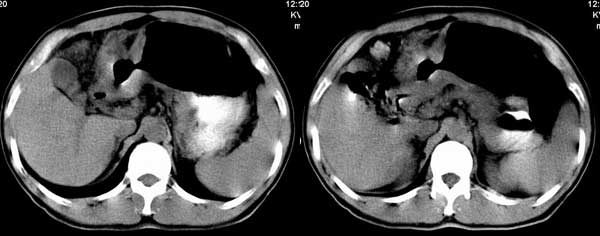

以下是引用听蝉观竹在2005-2-15 23:30:28的发言:[br]胃窦癌。[br]建议做胃镜检查并活检。

以下是引用大鹏在2005-2-16 16:14:44的发言:[br]我院用俯卧位显示胃窦部效果很好.[em4][emb26]